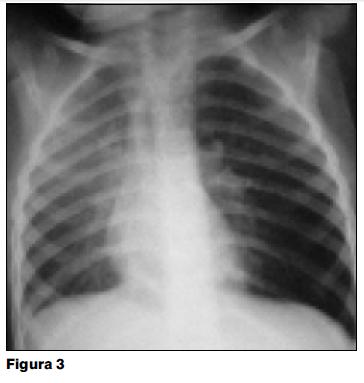

A los 8 días del alta reingresa por fiebre persistente. En la nueva radiografía persiste la consolidación parenquimatosa derecha y colapso total de los segmentos atelectasiados (figura 2). Durante esta internación presenta un acceso de tos cianozante, con crisis broncobstructiva severa. Este episodio, de breve duración, cede con oxigenoterapia y broncodilatadores. Al examen luego del episodio se destaca hipoventilación franca en la mitad inferior del hemotórax izquierdo. En la radiografía posterior a dicho episodio se observa hiperinsuflación del pulmón izquierdo con pulmonocele retroesternal y desplazamiento mediastinal contralateral, pulmón derecho sin imágenes de atelectasia ni consolidación parenquimatosa (figura 3).